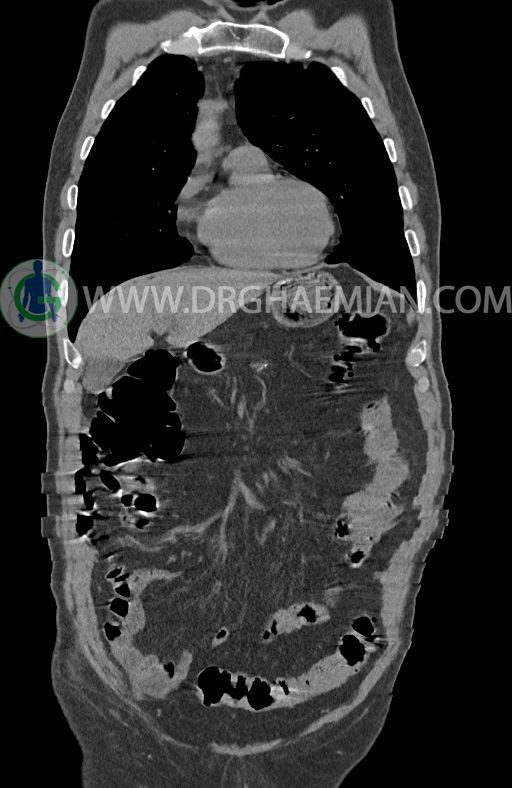

در سی تی اسکن اسپیرال ریه ها و مدیاستن، شکم و لگن با و بدون کنتراست وریدی (مولتی دیدکتور 16 با مقاطع ظریف و بازسازی کرونال) :

پلورال افیوژن، جابجایی محتویات مدیاستن، کلسیفیکاسیون، کیست، فیبروز ریوی و Collection مشهود نیست.

حجم ریه ها، طرح برونکو واسکولر ریه ها، فیشر ها و هیلوم دو طرف طبیعی است.

ضایعه ای در کبد، کیسه صفرا، کلیه ها و آدرنالها مشهود نیست.

ضایعه ای در معده ، روده باریک و کولون مشهود نیست .

مایع آزاد در حفره شکم و لگن رویت نمی شود.

–افزایش ضخامت تومورال دیستال مری و GEJ در سگمانی به طول 4cm-5cm (T2 or T3)

–آتروفی نسبی پانکراس همراه با فوکوس های کلسیفیه ی منتشر پارانشیم مطرح کننده ی پانکراتیت مزمن

نتیجه : T(2or3)/N2/M0